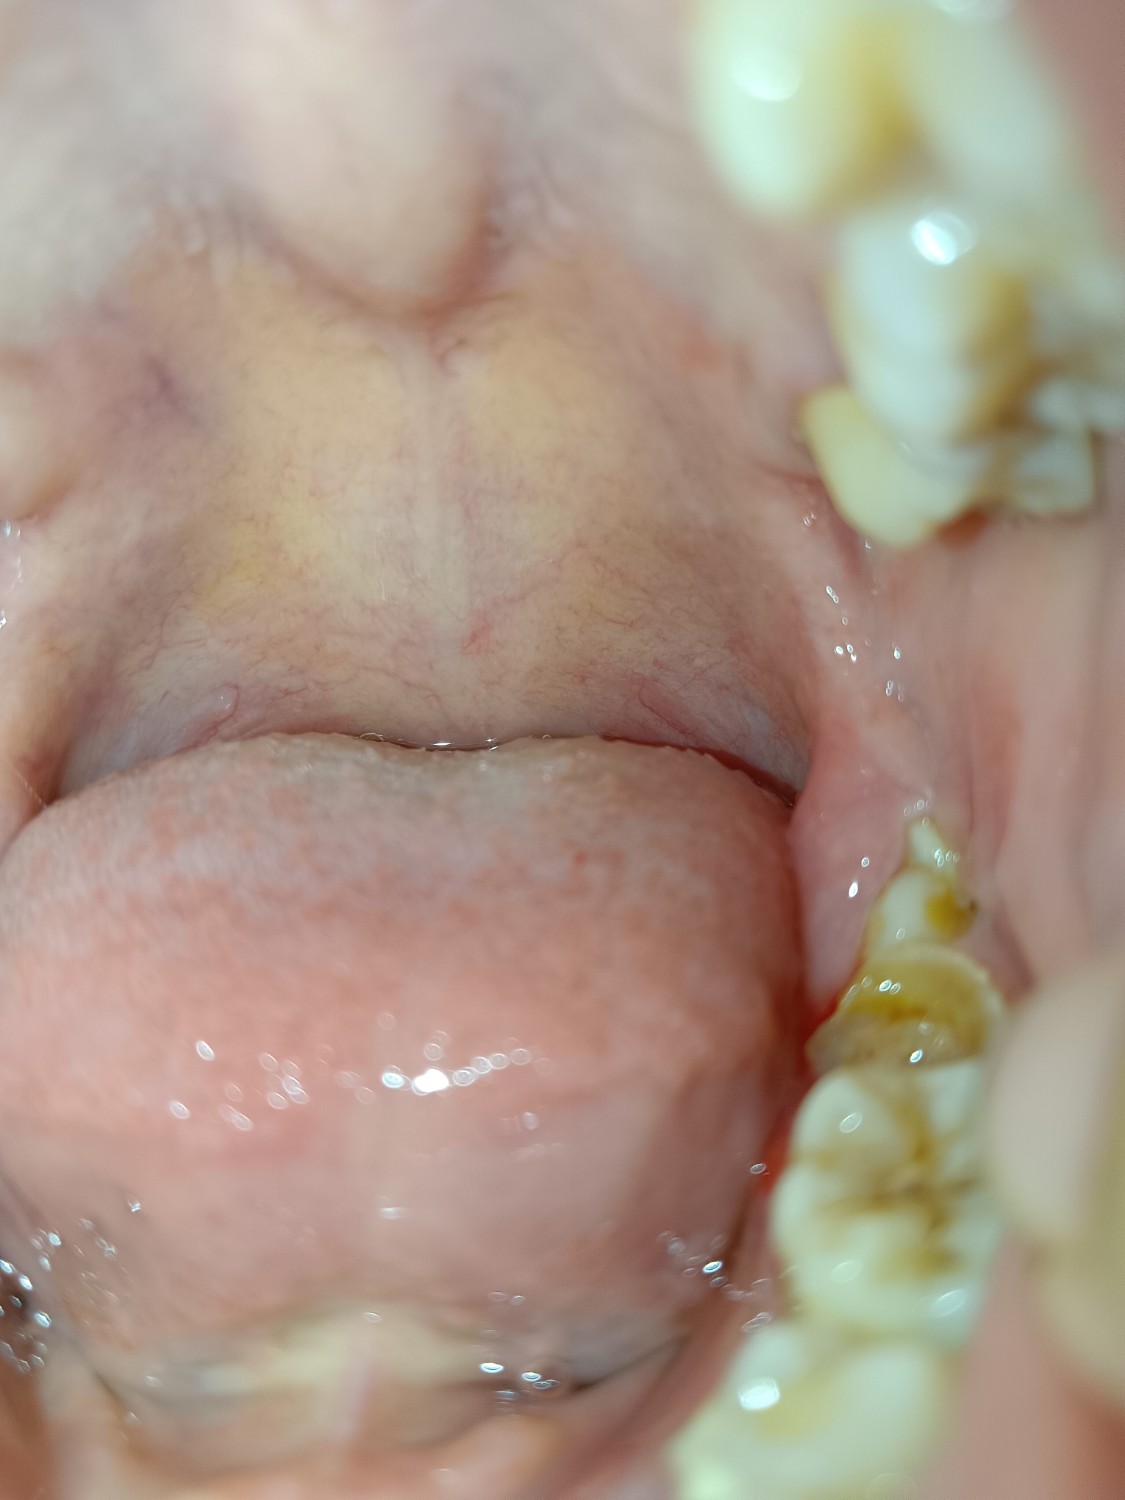

รบกวนช่วยเหลือหน่อยค่ะ

ทันตกรรม

ทันตแพทย์

ต้องจัดการยังไงดี

เป็นติ่งเหงือกที่ฟันคุด ทำยังไงดี?